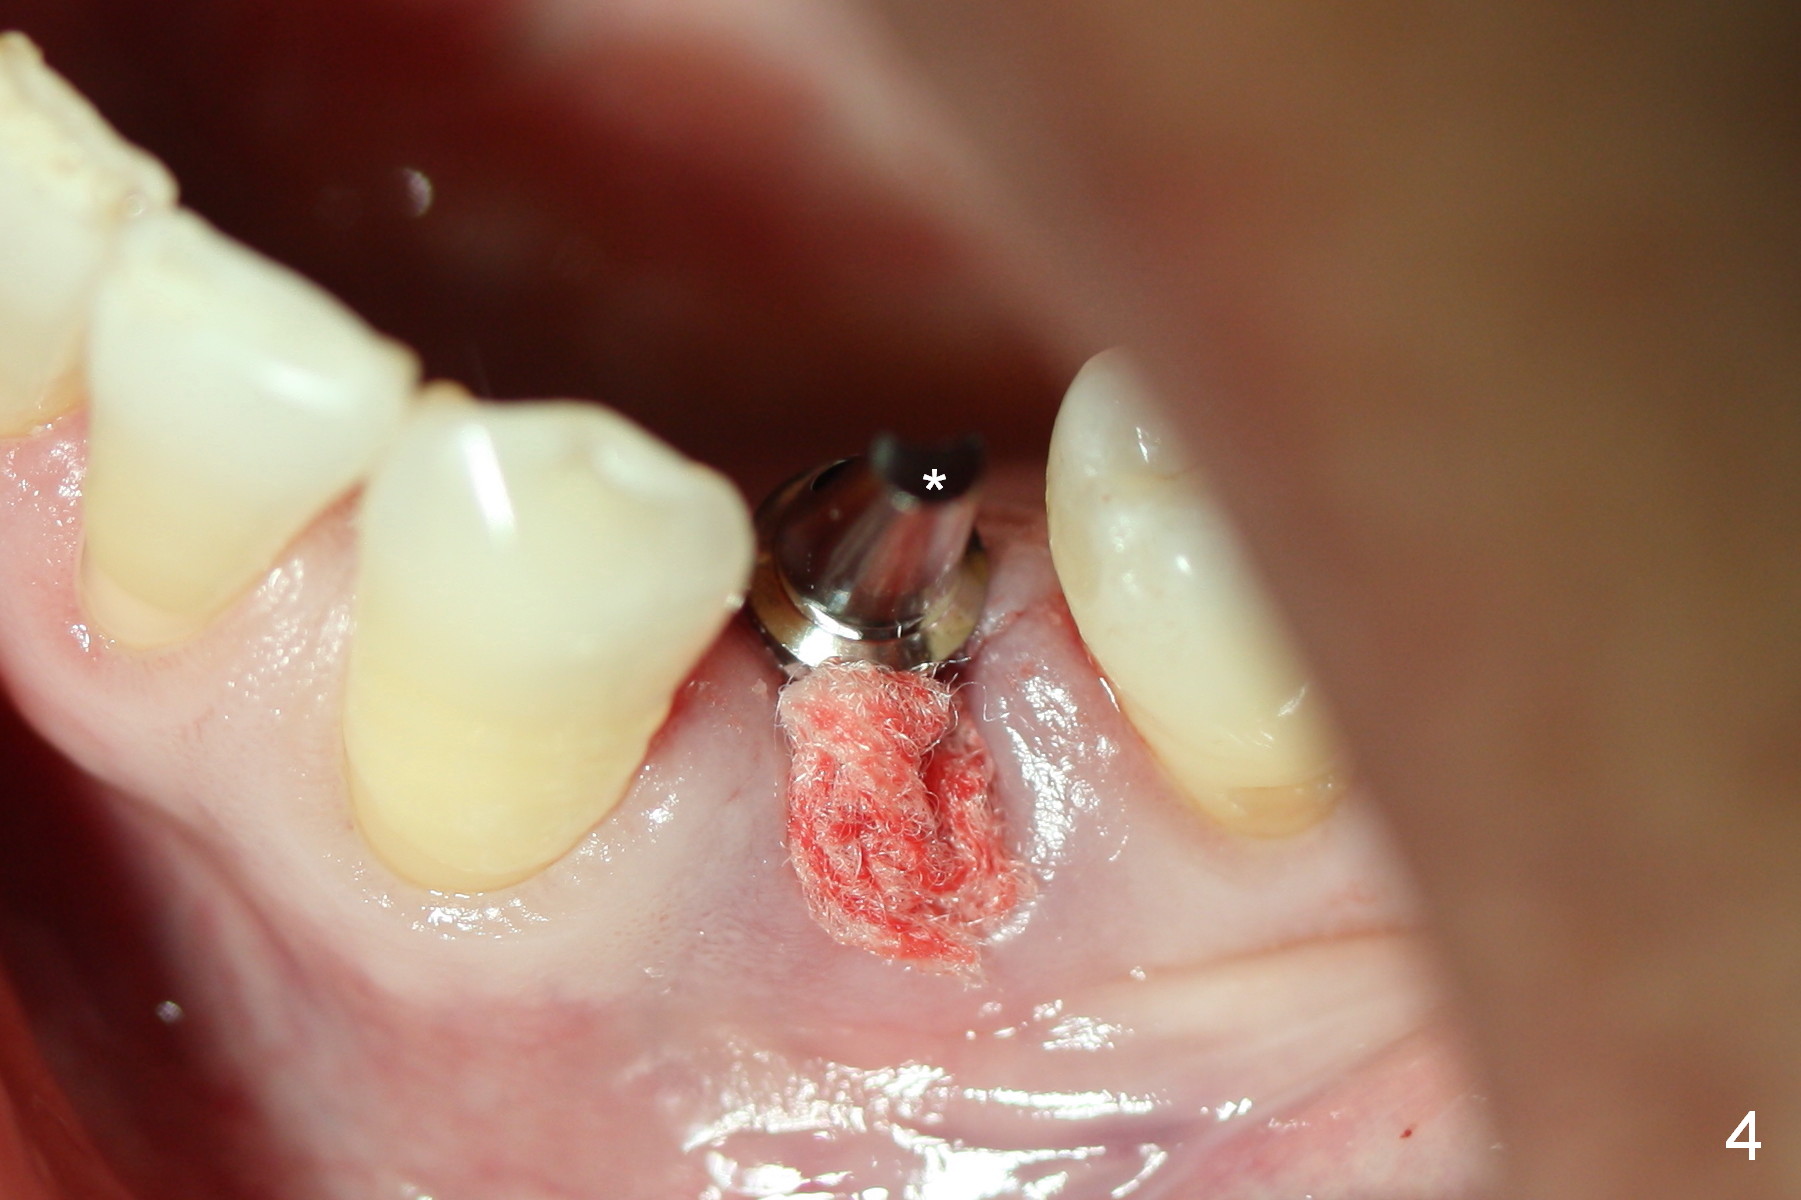

The residual root at #21 seems to be buccally positioned (Fig.1 *). The initial osteotomy is established with the 1.6 mm drill at 11 mm (Fig.2). Later the depth increases to 13 mm. The initial osteotomy is found to be too lingual, but experience shows that as osteotomy increases in diameter, the trajectory would shift buccally due to the thick lingual plate (slope). When 3.3 mm Magic drill reaches 11 mm, the patient feels pain. It is probably due to the dense bone. A 4x11 mm IBS implant cannot be seated due to high torque; it is removed. The osteotomy is increased with 3.8 mm drill. The implant is re-seated with >55 Ncm; it is over-lingually placed. Due to failure to seat the implant driver completely, the implant cannot be un-torqued. A 4.5 mm 15° angled abutment (3 mm cuff) is placed for immediate provisional (Fig.3,4 *).

The implant seems to have osteointegrated 4 months postop (Fig.9). When a permanent crown is fabricated, it should have normal occlusal and buccal contour (from Fig.11 (provisional) to 12 red and black curved lines) as well as the buccal cervical extension (Fig.12 to cover the buccal gingiva (Fig.10 *). If the lingual margin of the abutment is too prominent, return the case and the abutment will be changed to the one with 2 mm cuff (existing 3 mm). The lingual margin of the abutment will be trimmed. The patient is not pleased with the short buccal margin of the crown after cementation (Fig.13). In fact the provisional should have been fabricated so that the its buccal margin should be subgingival and within the gingival outline. It may prevent buccal plate collapse. In fact the crown dislodges 1 year post cementation. The lingual margin is prep lower to increase the abutment height. Impression is taken. Although the access hole is unnecessary for cementation, it acts as an escape hole so that there is no excess cement cervically (Fig.14-18).